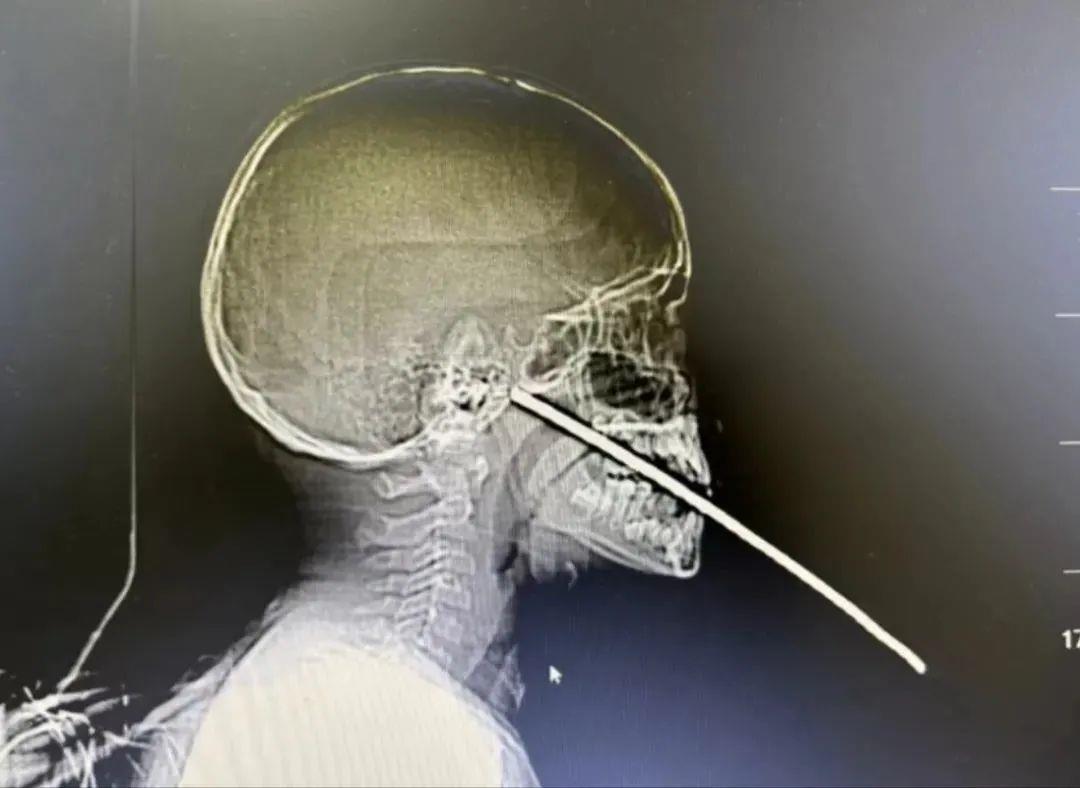

7月14日,云南省保山市一9岁男孩在玩耍时不慎摔倒,嘴巴被一根约1米长的钢筋插入,无法进行CT检查和后续治疗,医院急诊求助消防协助救治。

根据现场情况,1名消防员负责安抚小男孩,2名消防员在医生指导下利用断线钳将钢筋稳固,1名消防员则利用钢筋速断器剪断钢筋。

经过10分钟的紧张救援,消防员成功将钢筋剪断,为医院下一步急救赢得了时间和条件。